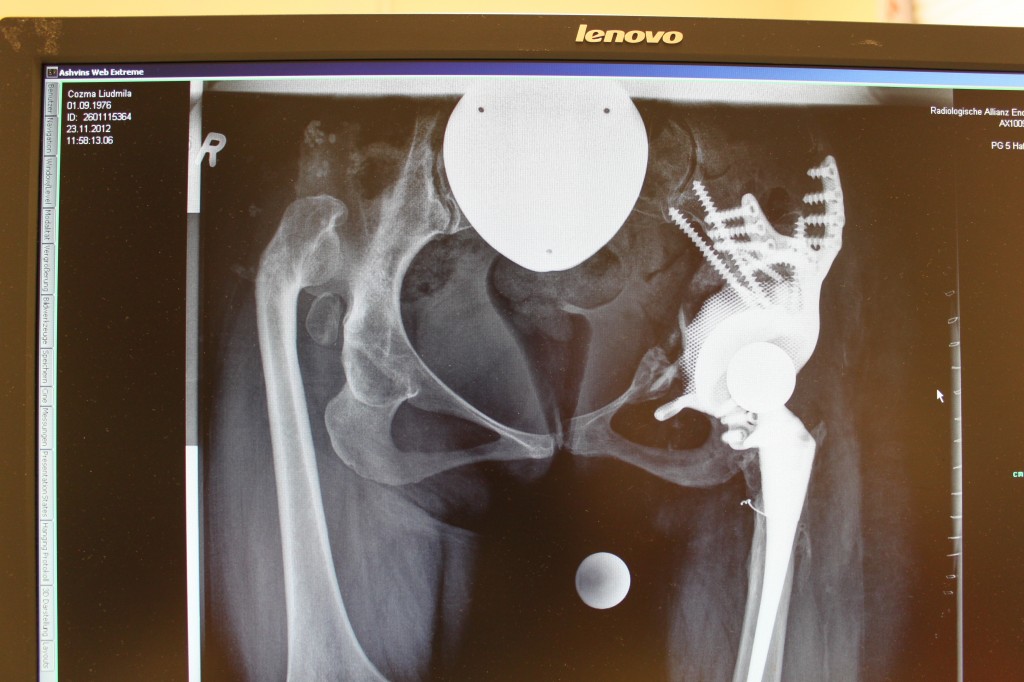

Эндопротезирование тазобедренного сустава — операция по замене поврежденной головки бедренной кости сустава на искусственный имплант.

Операция по замене тазобедренного сустава затрагивает подушечку и суставную часть тазобедренного сустава, и ограничение подвижности позволяет тазобедренному суставу правильно срастись.